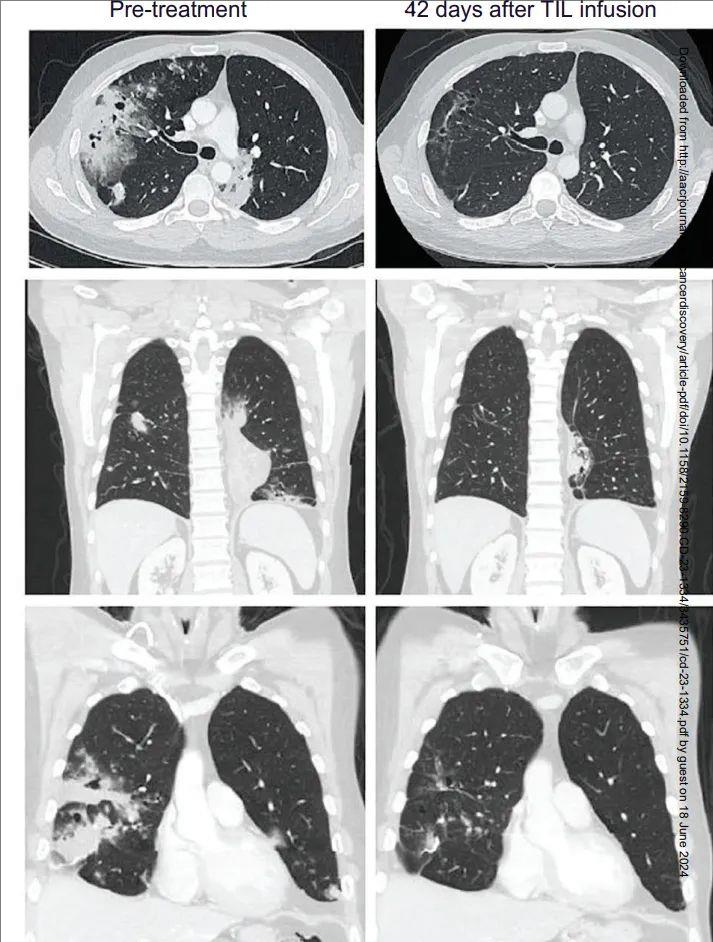

41岁M先生确诊为晚期粘液性肺腺癌,存在KRAS G12D突变,PD-L1表达率为0%,在经过包括卡铂、紫杉醇和派姆单抗在内的三线治疗后病情出现进展。接受TIL治疗后6周病灶显著缩小,12周的影响检查显示,肿瘤竟然缩小了81%!

这项研究数据之所以被认为意义重大,是因为从历史数据看,在化疗进展后接受抗癌“神药”PD-1的有效率也仅为20%左右,而TILs疗法对于化疗和PD-1都耐药的极晚期患者还能达到21.4%,并且还有一名患者肿瘤全部消失!说明这种新型的免疫疗法潜力巨大,是一款有望超越PD-1的更强免疫疗法,给临床上各种治疗耐药后的患者提供了新的选择和希望!